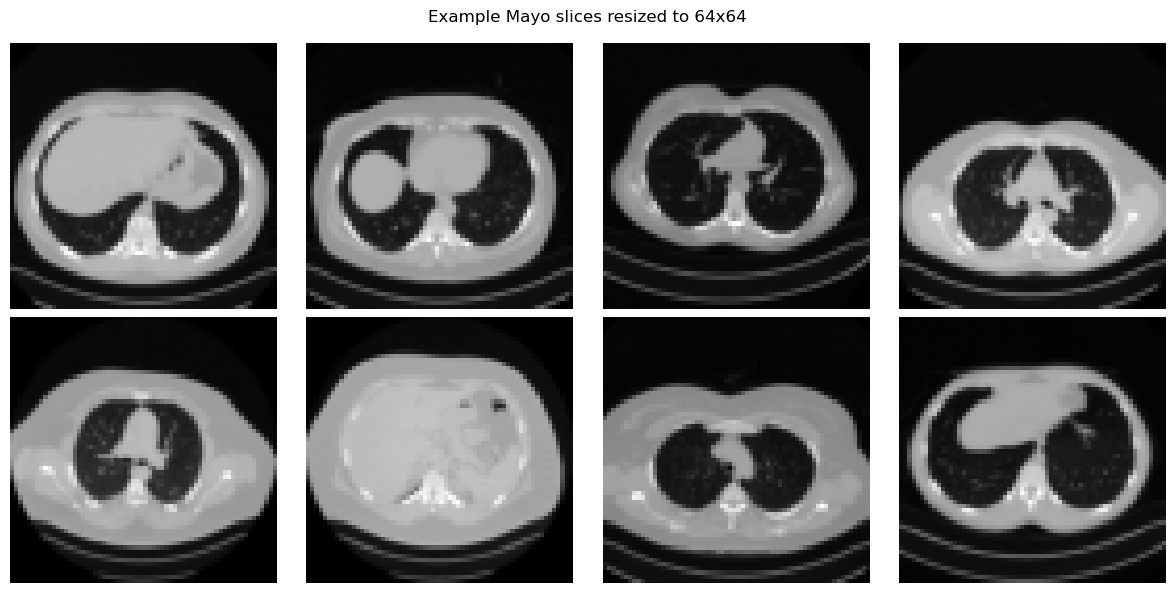

In this notebook we resize the Mayo images to \(64 \times 64\) when training VAEs and GANs. This keeps the code light enough for teaching purposes while preserving the main algorithmic ideas.

x_batch = next(iter(train_loader))

show_batch(x_batch[:8], 'Example Mayo slices resized to 64x64')

Device: cuda

Training images: 3306

Test images: 327